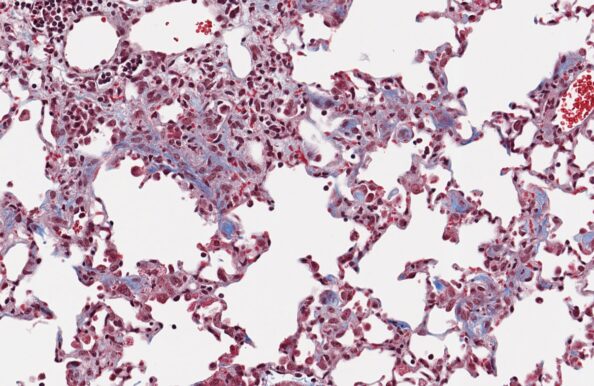

자동화된 AI 기반 조직학적 결과 평가

구브라는 폐활량 및 체적 측정법(Plethysmography)으로 검증된 블레오마이신 유도 IPF 마우스 모델을 제공합니다. 폐 질환 연구에 최적화된 모델과 고객 맞춤형 연구 디자인을 통해 폐 섬유증 대상 약물의 효능을 평가하기 위한 치료적 개입을 실현합니다.

Ashcroft 점수화

정량적 조직학 검사

AI 기반의 Ashcroft 병리학적 점수화

- AI 기반의 Ashcroft 병리학적 점수화